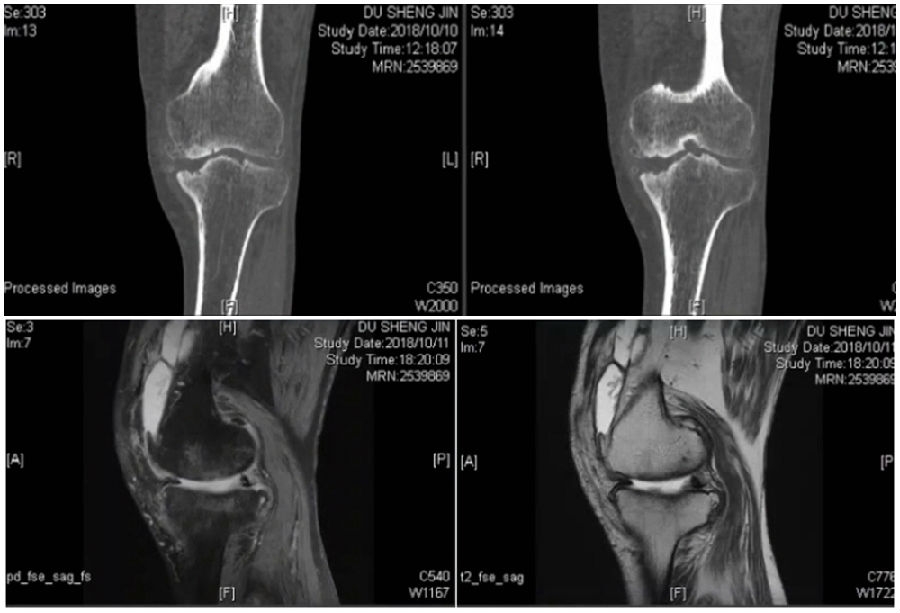

典型病例,男性,57岁,农民,左膝疼痛3年。

术前

术前影像资料

术前MRI